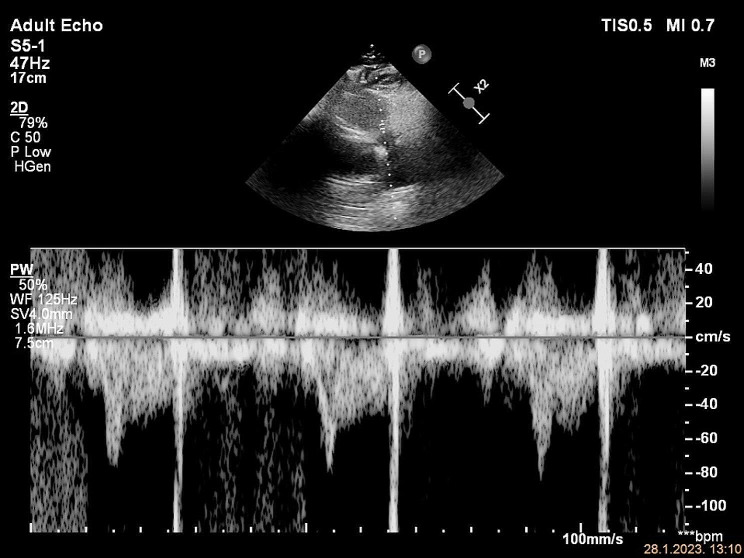

Background: Pulmonary embolism (PE) is one of the most challenging diagnoses in emergency medicine, mainly because symptoms range from asymptomatic disease to sudden death. The role of echocardiography in the workup of suspected PE has been supportive and used primarily to assess the right ventricular (RV) size and function, which is important for risk stratification. Several echocardiographic parameters described in the literature lack the desired accuracy. Recently, a potential value of less well-recognized RV outflow tract (RVOT) Doppler variables has been reported. The early systolic notching (ESN) pattern was observed in 92% of patients with high and intermediate risk PE, making it a promising sign in selected PE patients.

Case presentation: In this case series, we demonstrate a typical ESN pattern on RVOT Doppler evaluation in three patients with intermediate-risk PE presenting to our emergency department (ED). None of the patients had been previously diagnosed with pulmonary hypertension or other chronic pulmonary and cardiac disease. The pre-test probability was low. Massive proximal emboli were found on CT angiograms, involving pulmonary truncus or main pulmonary arteries. Previously, the ESN pattern was identified on a focused echocardiogram, which was the only echocardiographic indicator of increased pulmonary vascular resistance.

Conclusions: RVOT Doppler flow pattern of ESN has potential clinical utility for the detection of PE in ED patients. ESN could identify patients at higher risk, which are otherwise stratified as low risk according to the latest guidelines. Moreover, this case series illustrates that even in the absence of other echocardiographic findings of RV strain, the presence of ESN should alert to the possibility of acute PE. Further prospective studies are needed to assess its diagnostic value in a selected subgroup of patients, similar to the cases presented, that would have no other obvious reason for the altered RVOT Doppler curve.